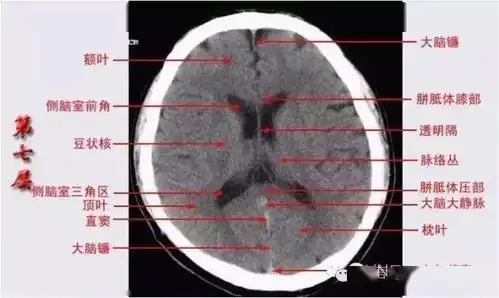

颅脑ct解剖口诀及彩色解剖图